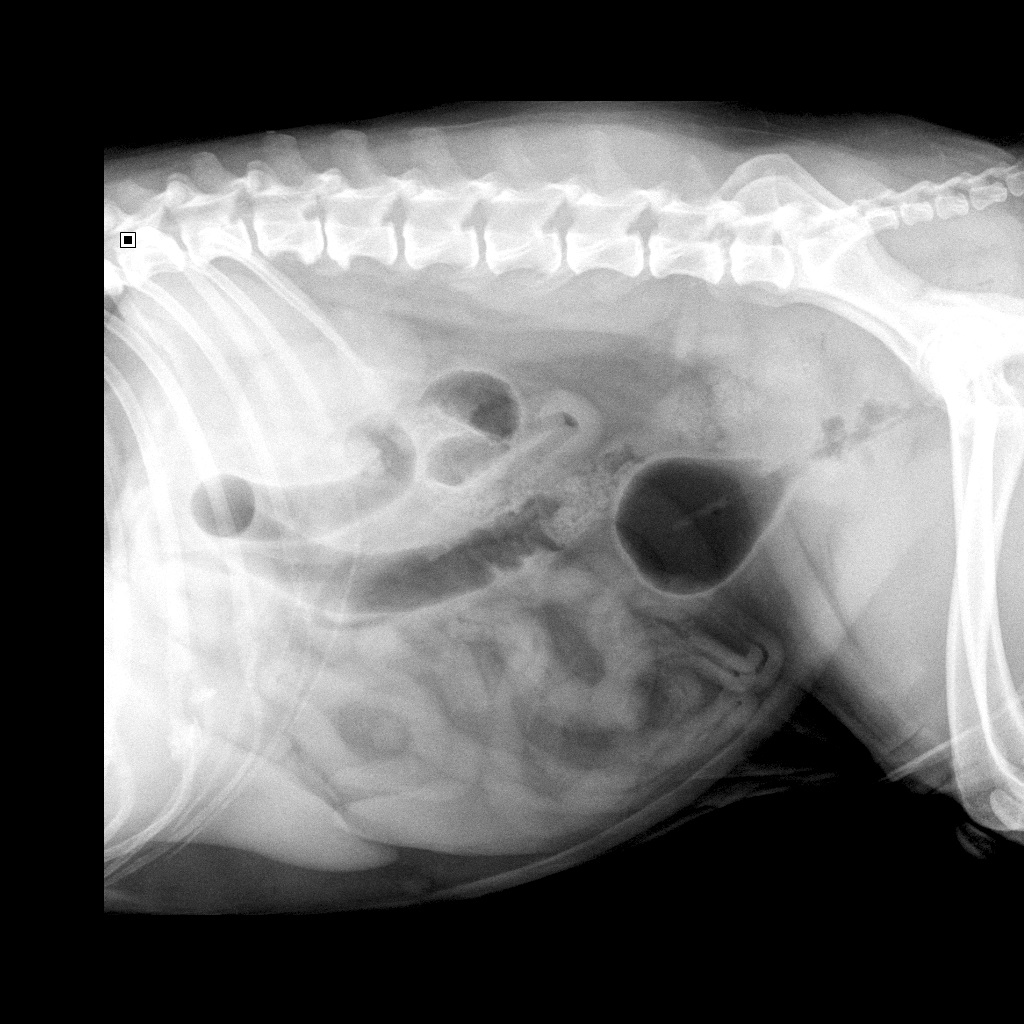

Duidelijk twee 'bollen' te zien waar er maar één (blaas) zichtbaar had mogen zijn:

rode cirkel is blaas

zwarte cirkel is prostaat